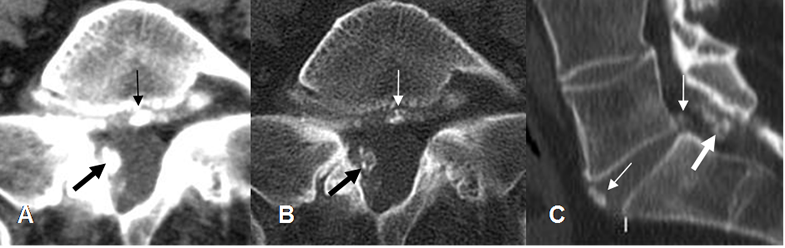

Fig 53. Canal estrecho central mixto.

A: TAC axial en ventana de tejido, B: TAC axial en ventana osea y TAC reconstrucción sagital. Canal estrecho mixto, con prominencia del disco, el cual está calcificado. (Flechas delgadas) y osteofito en la parte medial de la lámina derecha, que comprime el saco dural. (Flecha gruesa).